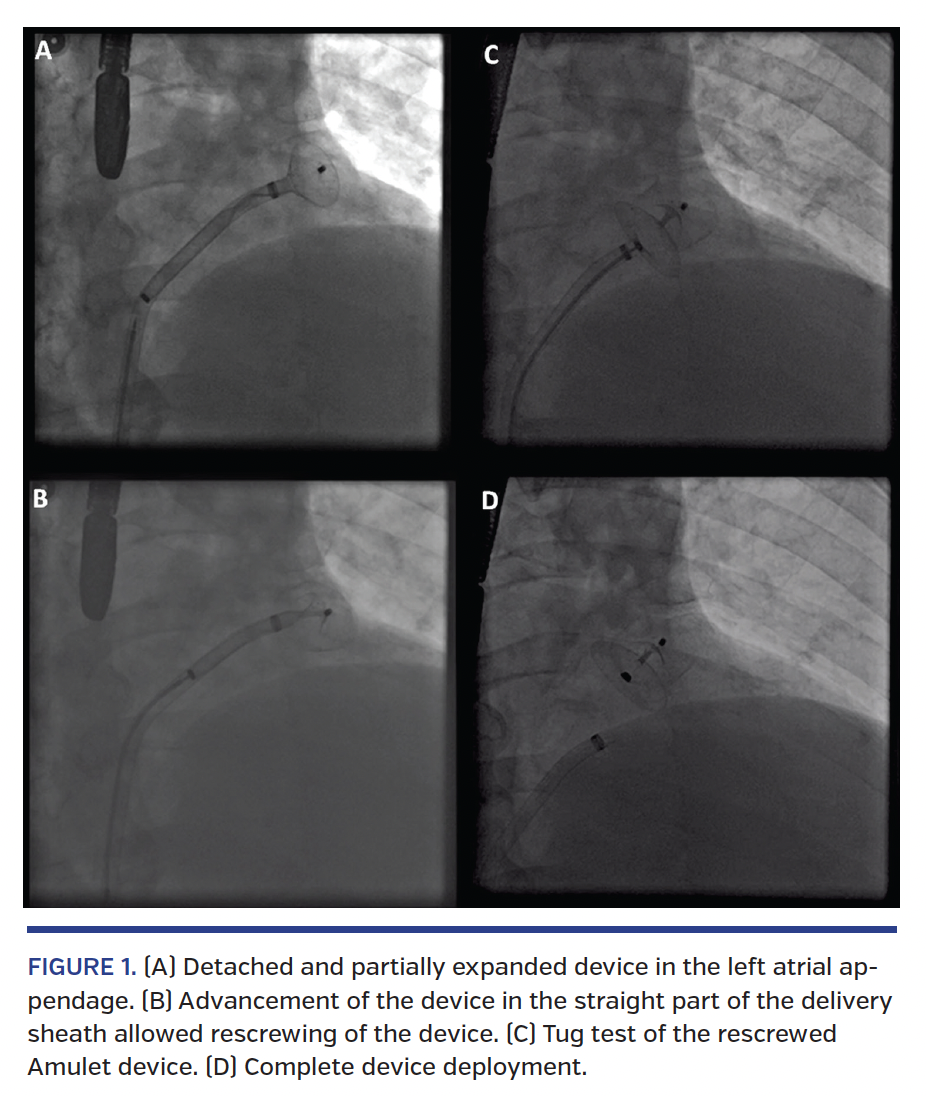

A 76-year-old patient was scheduled for percutaneous left atrial appendage (LAA) occlusion after a hemorrhagic stroke. After transseptal puncture and LAA sizing guided by transesophageal echocardiography, we planned to implant a 25 mm Amplatzer Amulet (St. Jude Medical) through a 14 Fr delivery sheath (DS). During the device advancement maneuver, fluoroscopy demonstrated the spontaneous unscrewing of the device from the delivery cable (DC) inside the DS at the level of its first bend; meanwhile, the lobe was already partially expanded in the LAA (Figure 1A). We unsuccessfully attempted to rescrew the device to the DC in the same position. Since the DS had an optimal position within the LAA, the most appropriate option was to push the device distally to complete the deployment (Video 1). At this point, with the proximal edge of the device now at the level of the straight tract of the DS between the two 45° bends, we gained coaxiality to successfully rescrew the device to the DC (Figure 1B). After the tug test, final device deployment was completed with an optimal result (Figures 1C and 1D; Videos 2 and 3).